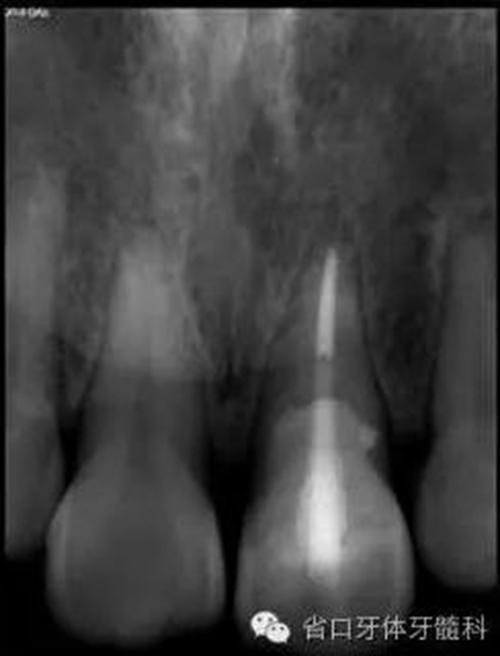

圖8. 21/行根管治療術(shù),保留根尖約5mm的根充物,根中上段預(yù)留空間以預(yù)備纖維樁道。